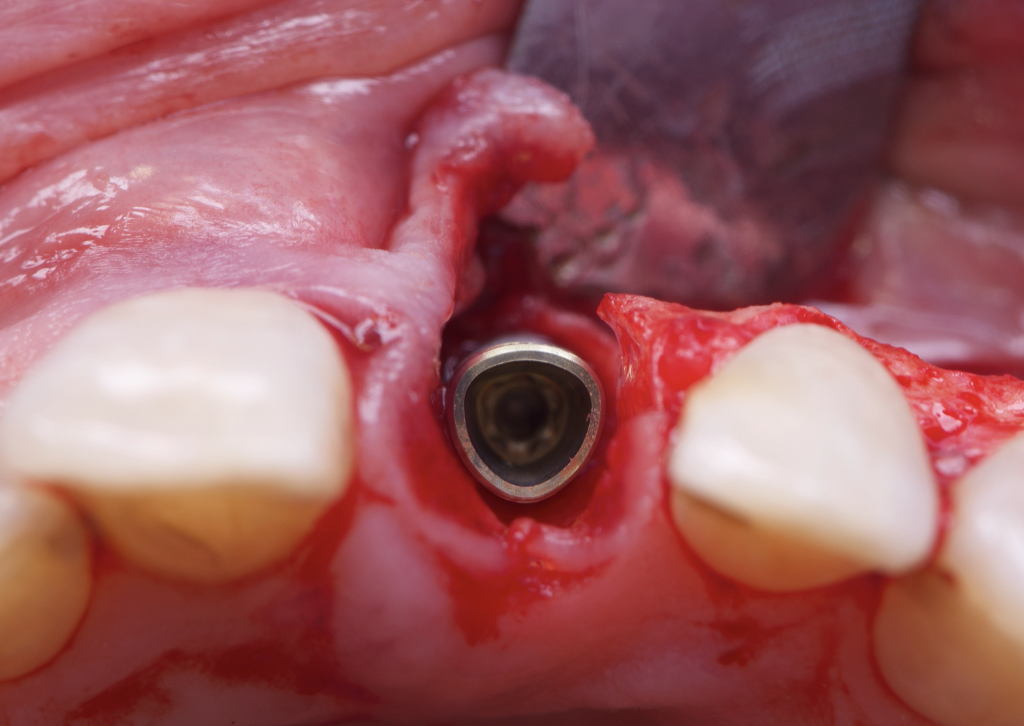

The surgical protocol began with the atraumatic extraction of tooth 1.1 to preserve as much of the alveolar socket as possible. Immediately following extraction, an N1 implant was placed into the socket using a guided surgical approach to ensure ideal three-dimensional positioning. The “one abutment one time” technique was applied to minimize soft tissue manipulation during the healing phase, which is particularly important in esthetic areas.

Given the significant buccal defect, guided bone regeneration (GBR) was performed simultaneously. A mixture of autologous bone and creos™ xenogain™ was applied to the defect and covered with a resorbable creos™ membrane to restore ridge width and support the buccal contour. In addition, a connective tissue graft was harvested and placed in the vestibular region to increase the thickness of keratinized mucosa. This combined approach addressed both hard and soft tissue deficiencies, providing the biological foundation for a stable and esthetic outcome.